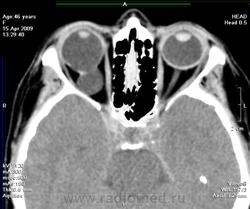

Орбитальная патология. Колобома. Nelas. +

Колобома